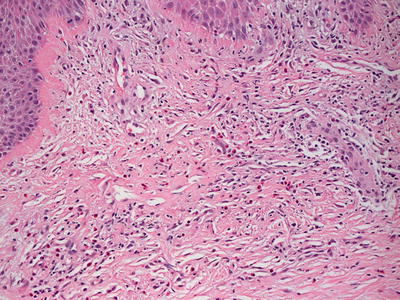

Fig. 14.7

The dermis demonstrates a diffuse and dense inflammatory infiltrate with abundant eosinophils in Norwegian scabies